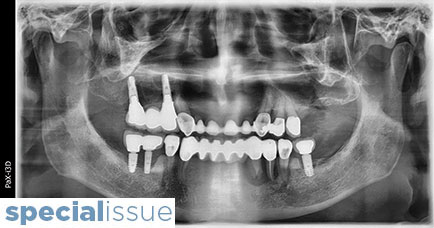

Peri-Implantitis Solea CO2 Laser: Clinical Case Report

OHSP-Kusek-main alternate text for this image

Introduction According to the Seventh European Workshop, 15-30% of all implants placed will develop peri-implantitis. Three million people have implants and this number is growing by 500,000 a year. Thus, peri-implantitis cases will grow up to 450,000 with an additional 75,000 which are expected to occur annually. 1 Clinicians will need to find appropriate treatment … Read more